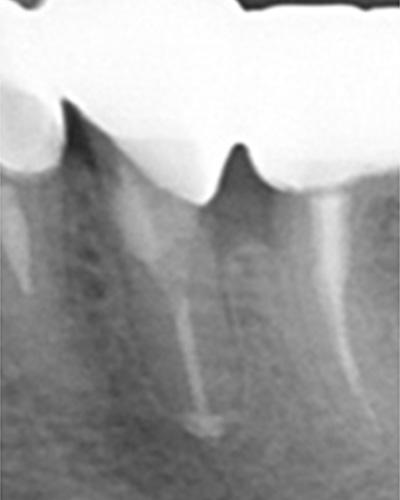

下の写真を見てください。この神経取れると思いますか。

本物の歯の神経の管を染めて、その走行を調べた写真です。複雑怪奇です。実際、この神経を全部きれいにとり切るのは不可能です。

患者さんは、神経を取るというと一本の糸をすーと引くと取れてくるようなイメージをお持ちのようです。私も歯科医になる前はそんなイメージを持っていましたが、神経を取る処置はまるで難攻不落の敵に立ち向かうほどの忍耐力を必要とします。大臼歯などは2時間ぐらいかかることもあります。

こちらのレントゲン写真を見てください。どちらかの歯医者さんで神経を取っています。根管に入れる薬は白く映ります。赤矢印部分です。一番右側が模式図ですが、青い部分が薬、根っこの先の赤点が化膿している部分です。

薬がほとんど入っていないのがわかります。黄矢印部分です。青矢印まで薬が入らないといけないのですが、全く入っていません。その結果、根っこの先が黒くなっています。膿が貯まって化膿すると黒く写ってくるのです。

別な歯科医院で治してもらいました。薬が根の先まで入っているのがわかります(黄矢印)。 根尖の黒い影が消失しています(赤矢印)。骨が再生すると白く写るようになります。

ガッタパーチャポイントは、理想的には歯根(シコン)の先ピッタリが良いと言われています。

上の図にあるように神経の管に入れる薬が根尖(コンセン)まで入っていなかったり、途中までしか入っていなかったり、薬がスカスカだったりするとその空間にばい菌が繁殖して感染を起こします。

①の写真はどちらかの歯医者さんで神経を取ってもらったレントゲン写真です。根っこの中に薬が全く入っていません。

根の先を見ると小豆ぐらいの大きさの黒い影が見えます。根の中でばい菌が繫殖し感染を起こすとこのような黒い影ができます。黒い影の部分は膿(ウミ)が貯まっています。こうなると腫れて痛みが出てくるのです。

③、④の写真はそれを治した後のレントゲン写真とその模式図です。白く映っている薬が根の先まできちんと入っているのが確認できます。そして根の先にあった黒い影が消えているのが分かります。根の先の炎症が治って、骨が再生すると白く映るのです。

薬が真ん中までしか入っていないため、膿が貯まっている。

薬が根尖までしっかりはいっていない。